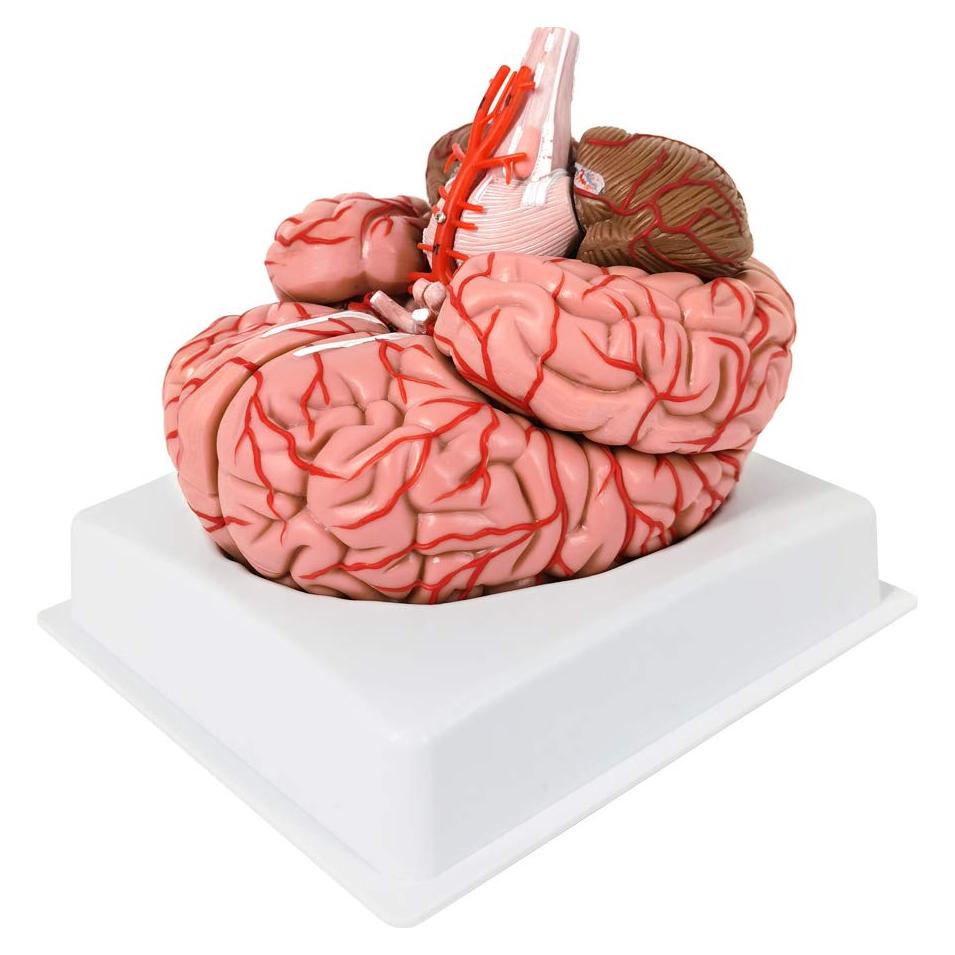

Modelos Anatómicos de Órganos marca Evotech (20 productos)

Modelos Anatómicos 3D EVOTECH SCIENTIFIC - Cuerpo, Corazón y Esqueleto